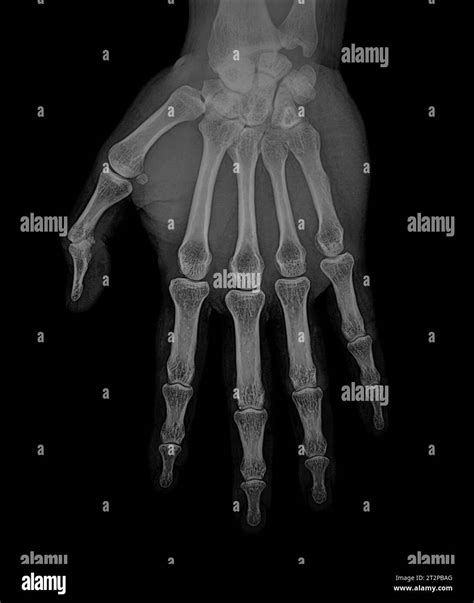

Understanding the intricacies of a Baby's Hand X Ray is crucial for healthcare professionals and parents alike. This diagnostic tool provides valuable insights into the skeletal structure and overall health of a baby's hand. Whether it's for diagnosing fractures, assessing bone development, or identifying congenital anomalies, a Baby's Hand X Ray plays a pivotal role in pediatric care.

A Baby’s Hand X Ray is a medical imaging technique that uses low doses of radiation to produce images of the bones and tissues in a baby’s hand. This non-invasive procedure helps doctors visualize the internal structures, detect any abnormalities, and make informed decisions about treatment.

Interpreting the results of a Baby’s Hand X Ray requires expertise in pediatric radiology. The radiologist will look for several key indicators:

• Bone Density: Assessing the density and structure of the bones.

• Fractures: Identifying any breaks or cracks in the bones.

• Joint Spaces: Evaluating the spaces between the bones to check for any abnormalities.

• Soft Tissue: Examining the soft tissues around the bones for any signs of swelling or injury.